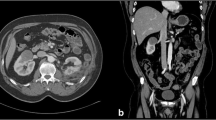

Digital Substraction Angiography

To visualize the dynamic perfusion, we performed DSA (AXIOM Artis FA®, Siemens, Germany) of the perfused kidneys with three pictures per second. For each DSA series, 20 ml of iodine contrast agent (Imeron® 300, Bracco Imaging, Italy) was injected to the perfusion system. Each DSA series (Figs. 2, 3) was reviewed by two independent and experienced interventional radiologists and two independent and experienced urologists in consensus.

Before NTIRE, we observed regular and physiological perfusion with flooding and complete draining off the vascular system of the renal parenchyma without any perfusion gaps. During (Figs. 2, 3) and after (Figs. 4, 5) NTIRE, we observed no relevant changes, such as extravasations, perfusion gaps, open areas, accumulations, or stases in the renal parenchyma. Conspicuous was a concentric wavelike fluctuation of the contrast agent, each based on the apex and basis of the nonisolated lower pole of the NTIRE single-needle bipolar probe, which appeared simultaneous to the NTIRE pulses (90/min), expanded around 1 cm and cleared away completely during perfusion (Fig. 3).

Overall it has to be noted that just major renal vessels, especially of the renal medulla, are detailed visible in DSA, whereas the vascular system of the renal cortex between the renal medulla and the renal capsule seems to be spared (Fig. 2). Because of that, in the following, these visible major vessels in DSA are defined as macrovascular system of the kidney.

This experimental study is the first radiological approach to examine the renal vascular system in the acute phase of NTIRE. Conventional DSA before, during, and after NTIRE as well as digital static angiography per high resolution X-ray imaging in low-kV exposure mammography technique after NTIRE were used in isolated, perfused, porcine, ex vivo kidneys. This enables a qualitative radiological examination of the NTIRE ablation zone closed and surrounded terminal macro- and microvascular bed of renal parenchyma in the acute phase. Referred to its typical anatomy of the renal vascular system, the DSA shows the renal macrovascular system with vasa renales, segmentales, interlobares, and arcuatae of the renal medulla and columns (Fig. 2), whereas the angiography in mammography technique additionally shows the renal microvascular system with vasa corticales, rectae spuriae, and rectae verae of the renal cortex and pyramids (Figs. 4, 5).